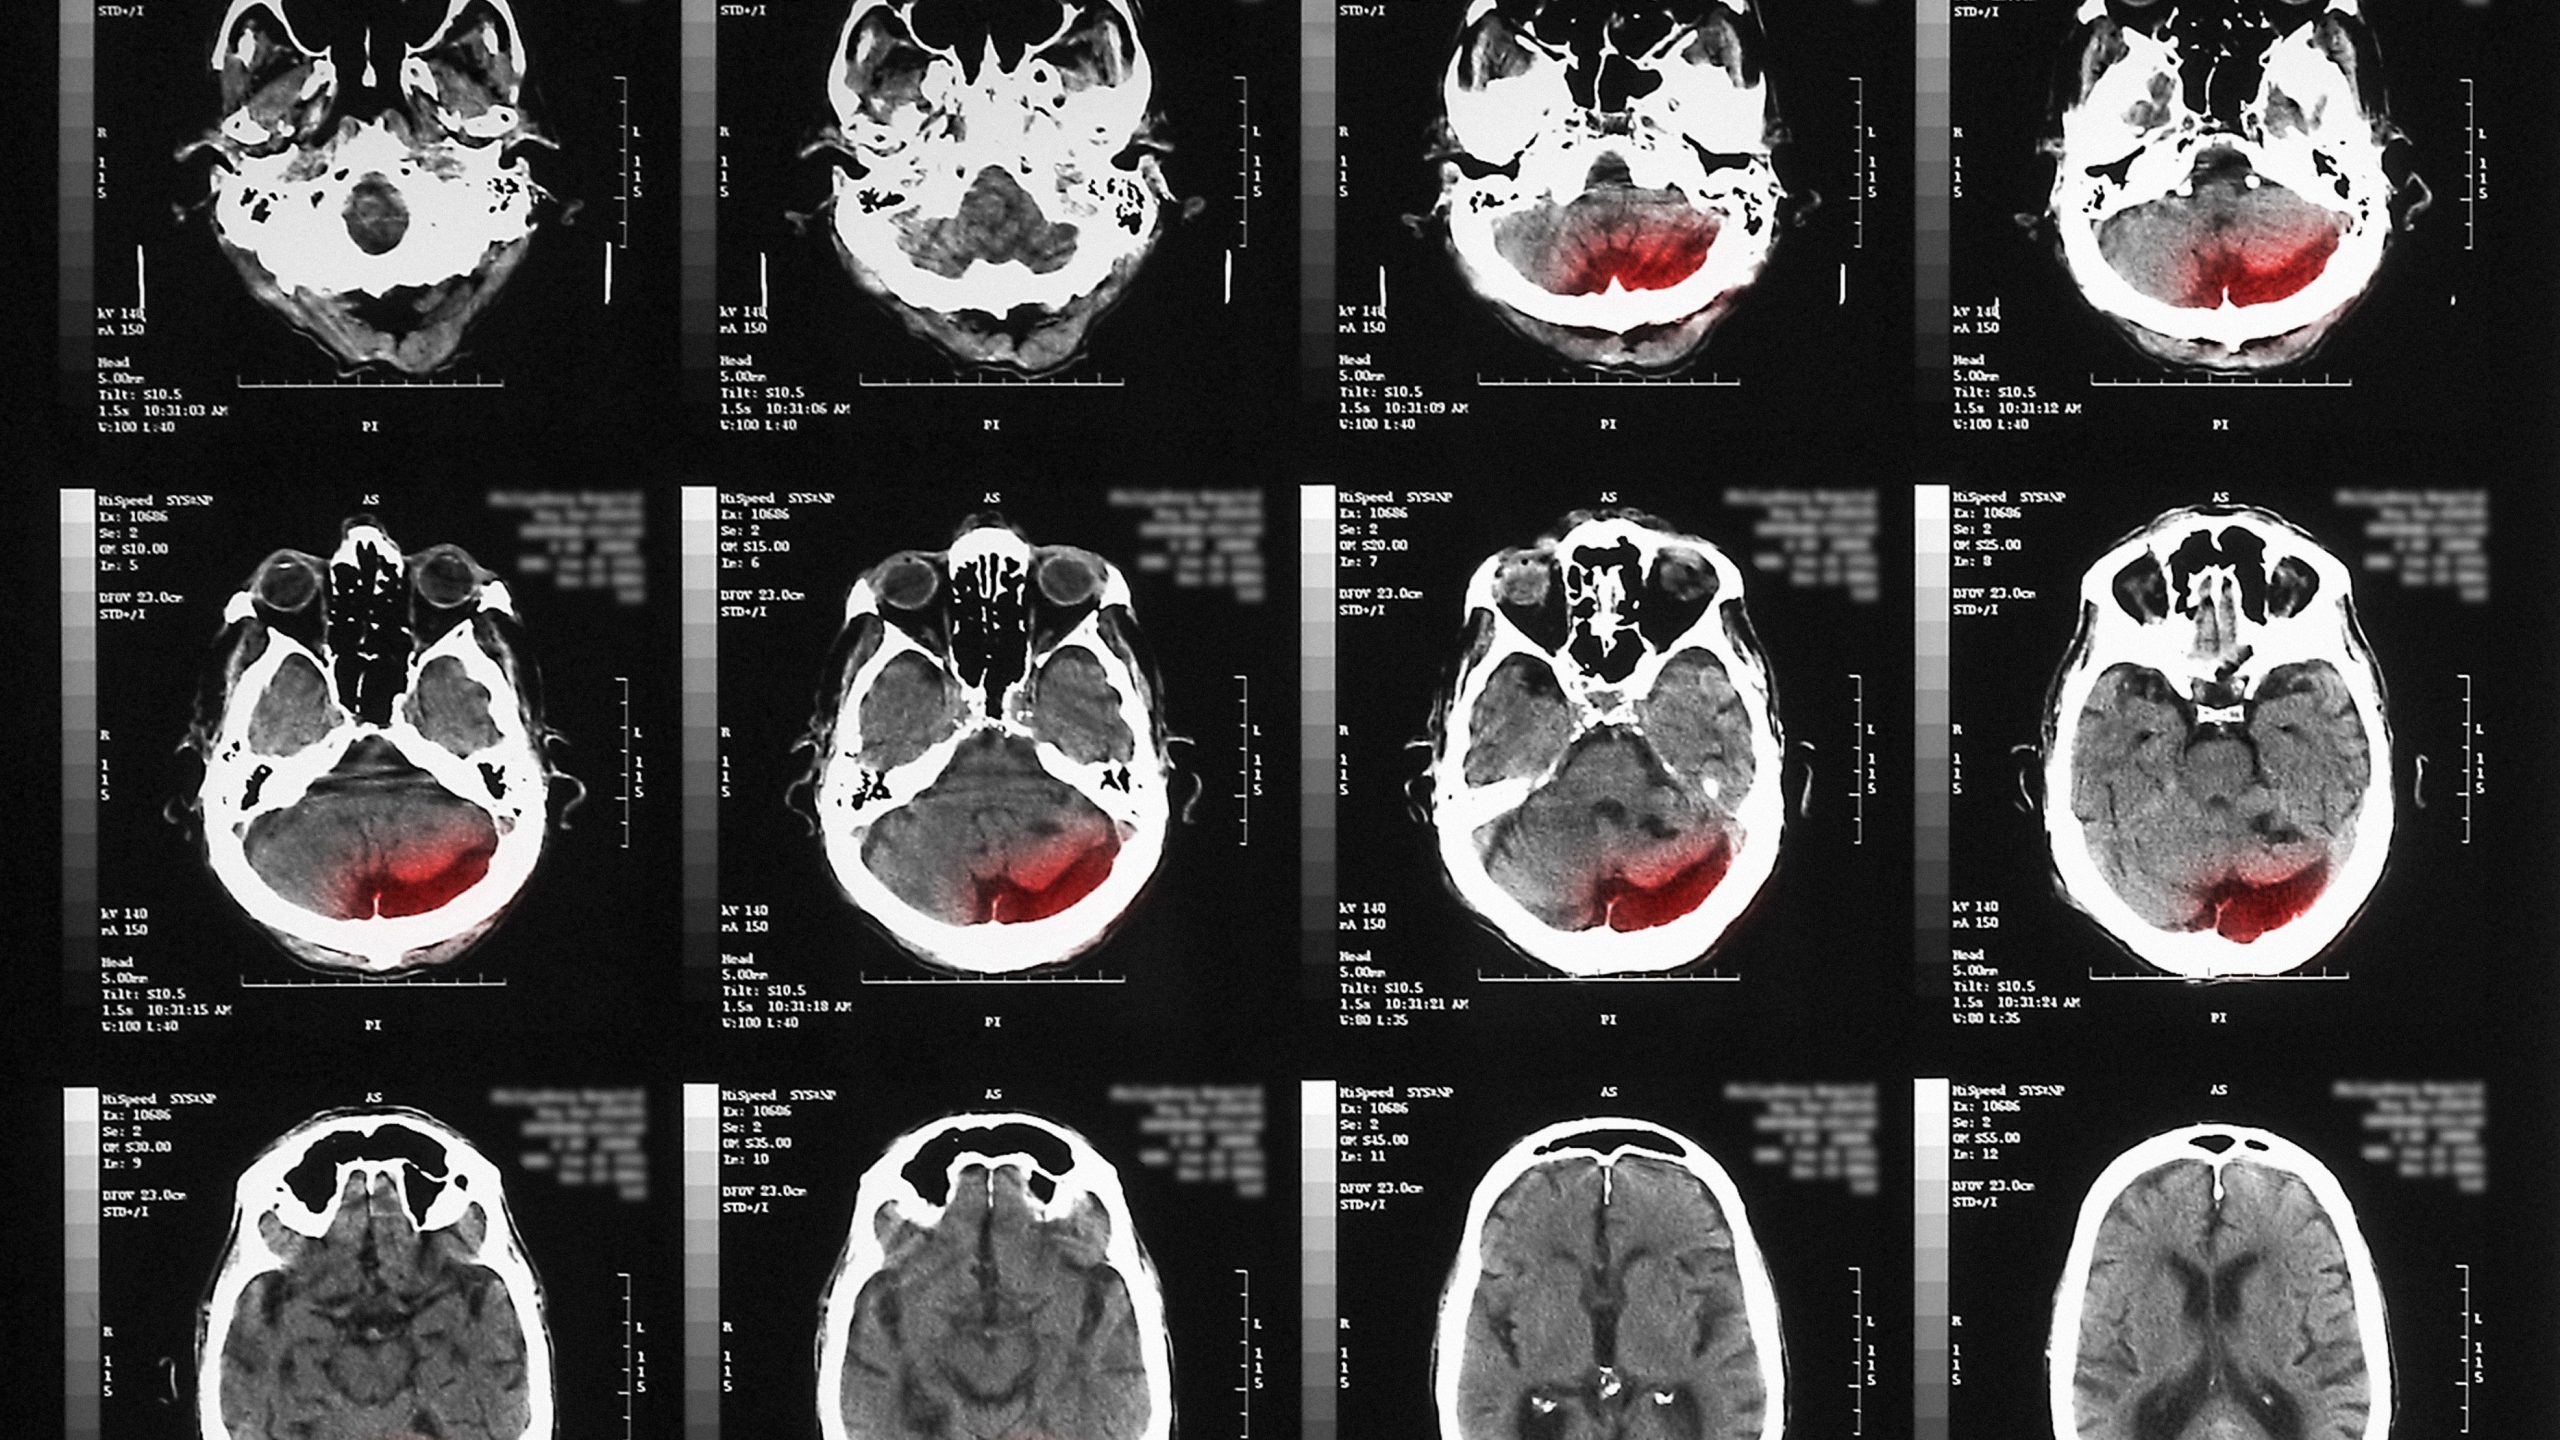

敵対的攻撃に関する研究の大部分では画像認識システムに焦点が当てられているが、深層学習をベースとする画像再構築システムにも同じような脆弱性がある。X線データやCTスキャン、MRIスキャンなどの医療用画像を再構築するのに、画像再構築システムを利用することの多い医療分野では特に問題となる。標的を絞った敵対的攻撃により、そうしたシステムが、実際には腫瘍のない箇所に腫瘍があるかのようにスキャン画像を再構築してしまう可能性があるのだ。